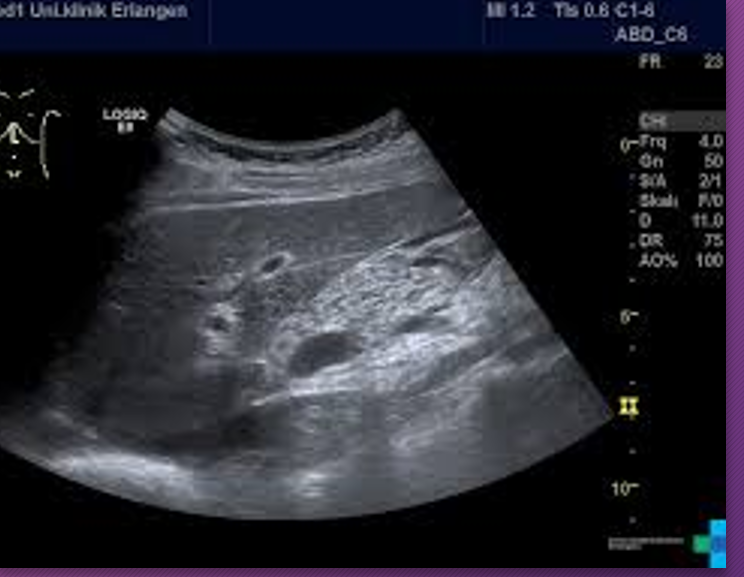

A _______ pancreatitis is an _______ process that spreads along _____ pathways, causing localized areas of diffuse inflammatory _____ of soft tissue that may proceed to necrosis and suppuration

phlegmonous; inflammatory; fascial; edema

______ pancreatitis occurs in ___-___ of patients with _____ pancreatitis

Phlegmonous; 18-20%; acute

Sonographically, phlegmonous tissue appears ______ in texture with good through-_____

hypoechoic; transmission

Sonographically, how does phlegmonous tissue appear?

Hypoechoic with good through transmission

Phlegmonous pancreatitis usually/commonly involves the ____ sac, ____ anterior _____ space, and transverse ______.